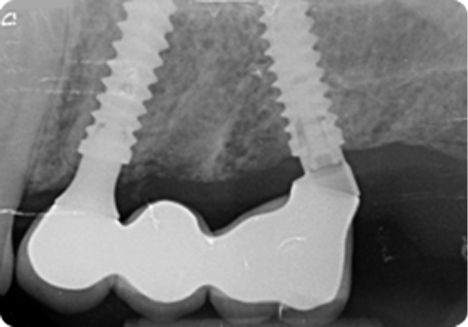

COLOCACIÓN

El implante Top DM está concebido para ser colocado de forma infraósea, minimizando la pérdida ósea marginal y mejorando el resultado estético de la restauración.

El protocolo de fresado es sumamente sencillo y rápido, pudiéndose colocar el implante con tan solo dos o tres fresas en la mayoría de los casos.